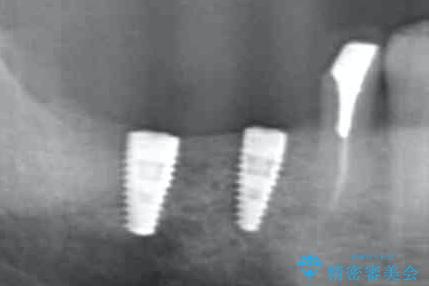

- 歯周病が進行し、根尖付近まで歯槽骨(歯を支える骨)の吸収が見られる歯の治療を希望され来院されました。

長期的な予後の見込めない奥歯の抜去を行い、骨と歯ぐきの治癒を待ち、インプラント治療を計画します。

- 88万円(インプラント2本分)費用は治療当時の料金となります

インプラント周囲には骨の増生を埋入時に同時に行っています。